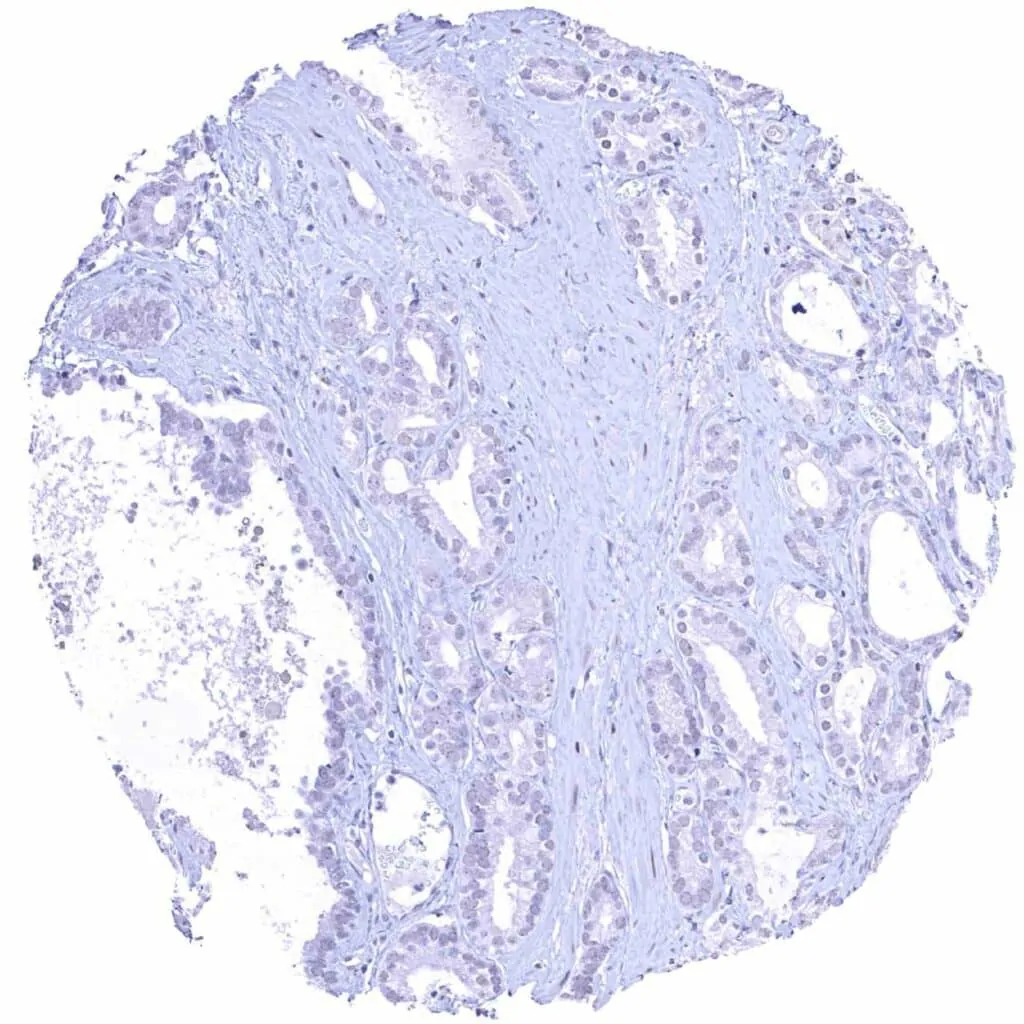

Prostate – Cyclin E1 negative adenocarcinoma (Gleason 3+3=6)